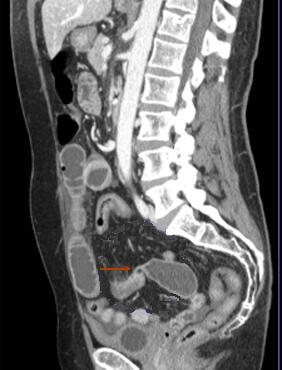

Image TDM en coupe

sagitale : Occlusion de l'intestin aigue avec

signe de bec de oiseaux ( fleche rouge ) et

dilatation intestinale en amont et signe de feces (

retention de feces au niveau de l'intestin sus -lesionelle |